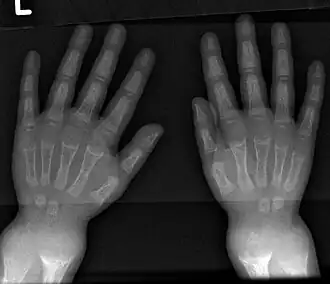

| X-ray of a two-year-old with rickets, demonstrating a marked bowing of the femurs and decreased bone density | |

An X-ray or radiograph of an advanced patient with rickets tends to present in a classic way: the bowed legs (outward curve of long bones of the legs) and a deformed chest. Changes in the skull also occur, causing a distinctive "square-headed" appearance known as "caput quadratum".[18] These deformities persist into adult life if not treated. Long-term consequences include permanent curvatures or disfiguration of the long bones, and a curved back.[19]